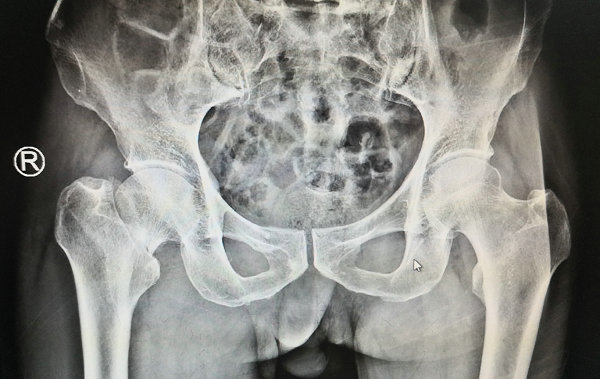

73岁的赵大爷两周前在家滑倒,一屁股坐在水泥地面上,当时只觉得左髋部疼痛,活动明显受限,稍一动就疼痛加重,在当地医院作了CT检查,显示左股骨颈骨折。家人随后把老人送来betway在线登陆治疗。

关节科蒋守海主任医师接诊了老人,进行了仔细检查与问诊,老人是左股骨颈骨折无疑。麻烦的是,赵大爷还有高血压、脑梗死病史,同时患有糖尿病和肾病综合症,对于这样一个身体多脏器都在走下坡路的老人,髋部骨折手术难度很大,但为了后期老人的生活质量,蒋主任还是决定为老人做这个手术。

术前